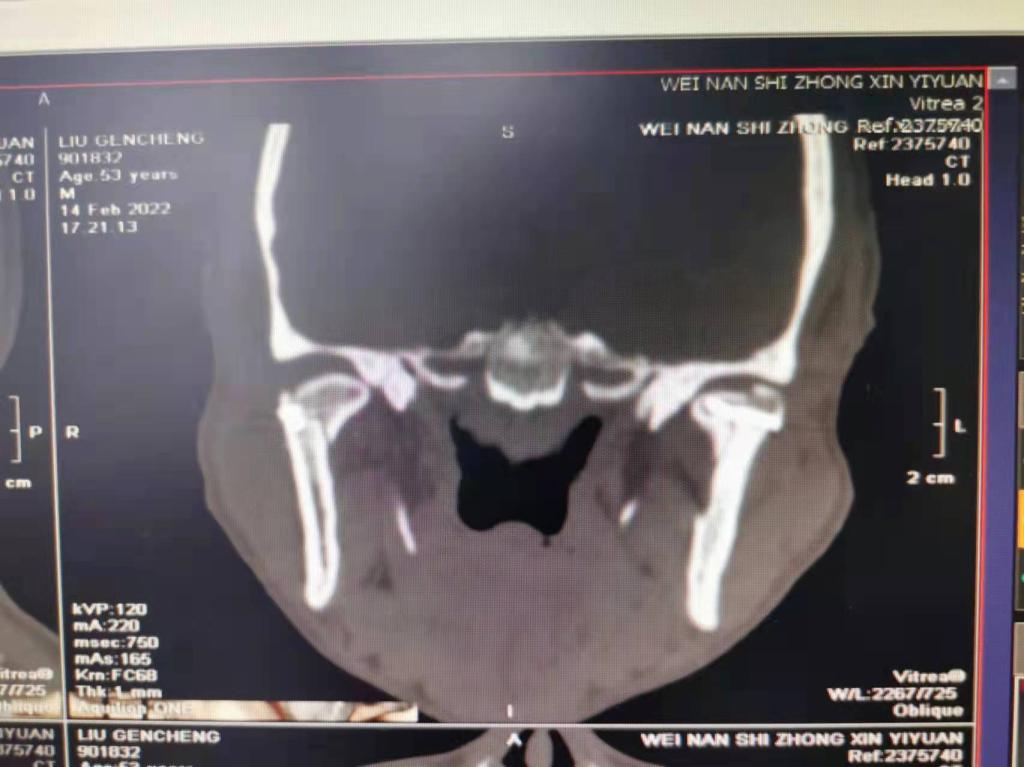

据了解,53岁的患者刘先生在1月25日当天走路不慎摔倒致下颌损伤,造成颏部软组织裂伤和张口困难,前往当地卫生院进行颏部裂伤清创缝合术。术后辗转到乐鱼在线登录入口口腔科门诊就诊,并进行颌面部CT检查提示为下颌颏部正中和双侧髁状突骨折,双侧下颌升支高度不一致,右侧较左侧变短1cm,张口重度困难,咬合关系错乱。刘先生因考虑在春节过后再入院治疗,于2月8日再次前来口腔科以“下颌骨骨折”收治人院。

口腔科主治医师蔺非非为患者入院后进行完善术前常规检查和颌间牵引恢复咬合关系。科主任李瑞春结合患者实际病情和检查结果认为,患者的髁突骨折在下颌骨骨折中所占比例较高,约为17.0%-36.3%。髁突骨折时,耳前区有明显的疼痛,局部肿胀、压痛。通过手指深入外耳道或在髁突部触诊,如张口时髁突运动消失,可能有骨折段移位。双侧低位骨折时,2个髁突均被翼外肌拉向前内方,双侧下颌支被拉向上方,可出现后牙早接触,前牙开秴。髁状突骨折易引起下颌后缩,张口困难,咬合关系错乱,关节强直等并发症。考虑患者系陈旧性骨折应尽早实施手术,避免骨折导致的张口困难、关节强直等并发症。因患者已经错过最佳治疗时期,决定尽快为患者进行手术治疗。

科主任李瑞春和主治医师蔺非非经过缜密的术前讨论和充分评估,手术在全身麻醉下进行,术中克服术野狭小操作不便困难,将下颌骨骨折完好对位,顺利地完成了"双侧髁状突和下颌颏部正中骨折切开复位内固定术"。术后检查患者面部对称,双侧下颌升支高度一致,咬合关系已恢复。